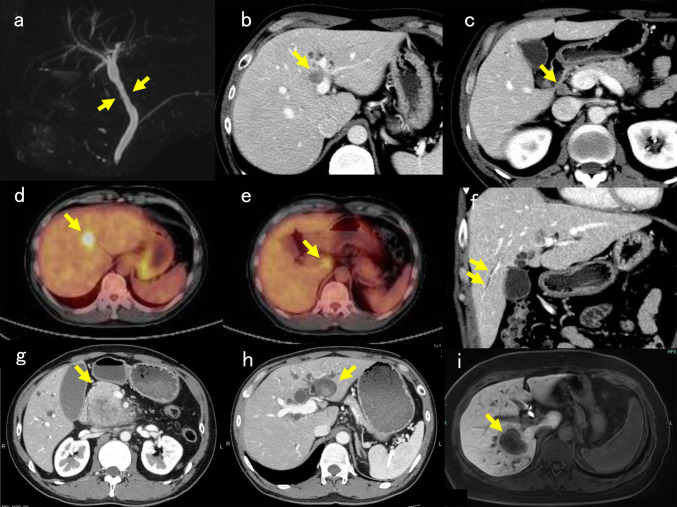

2014年,大阪一家印刷公司报告了17名因长期接触高浓度1,2-二氯丙烷和/或二氯甲烷而罹患职业性胆管癌的患者,此后又有5名患者被确诊患有此类胆管癌。五名患者中有四名是在定期体检或肝功能异常随访时发现胆管癌的。这五名患者几乎都有临床病理发现,如确诊时γ-谷氨酰转肽酶活性升高、肝内胆管区域性扩张而无肿瘤引起的梗阻、慢性胆管损伤以及胆管不同部位的癌前病变/早期癌变(胆管上皮内瘤变和胆管导管内乳头状瘤变)。这些结果与之前 17 例患者的结果相似。在印刷公司接触过 1,2 二氯丙烷的 95 名工人中,共有 22 人罹患胆管癌。在 22 名胆管癌患者中,18 名患者属于 19 名高接触率工人(≥ 1,500 ppm-年)。这些发现进一步加强了 1,2-二氯丙烷导致职业性胆管癌的理论。有必要对接触 1,2 二氯丙烷和/或二氯甲烷的工人进行定期健康检查,以发现此类胆管癌,因为潜在的致癌风险长期存在。

After the report of 17 patients with occupational cholangiocarcinoma caused by long-term exposure to high concentrations of 1,2-dichloropropane and/or dichloromethane in a printing company in Osaka in 2014, additional five patients were diagnosed to have such cholangiocarcinoma. Cholangiocarcinoma was detected during regular health examination or follow-up for liver dysfunction in four of the five patients. Nearly all five patients presented with clinicopathological findings such as an elevated γ-glutamyl transpeptidase activity at the diagnosis, regional dilatation of intrahepatic bile ducts without tumor-induced obstruction, chronic bile duct injury, and precancerous/early cancerous lesions (biliary intraepithelial neoplasia and intraductal papillary neoplasm of the bile duct) at various sites of the bile duct. These findings were similar to those of the previous 17 patients. In total, cholangiocarcinoma developed in 22 of 95 workers exposed to 1,2-dichloropropane in the printing company. Of 22 patients with cholangiocarcinoma, 18 patients were members of 19 high exposure workers (≥1,500 ppm-yr). These findings strengthen further the theory that 1,2-dichloropropane causes occupational cholangiocarcinoma. Regular health examination of workers exposed to 1,2-dichloropropane and/or dichloromethane is necessary to detect such cholangiocarcinoma because the potential of the carcinogenesis risk persists over the long term.